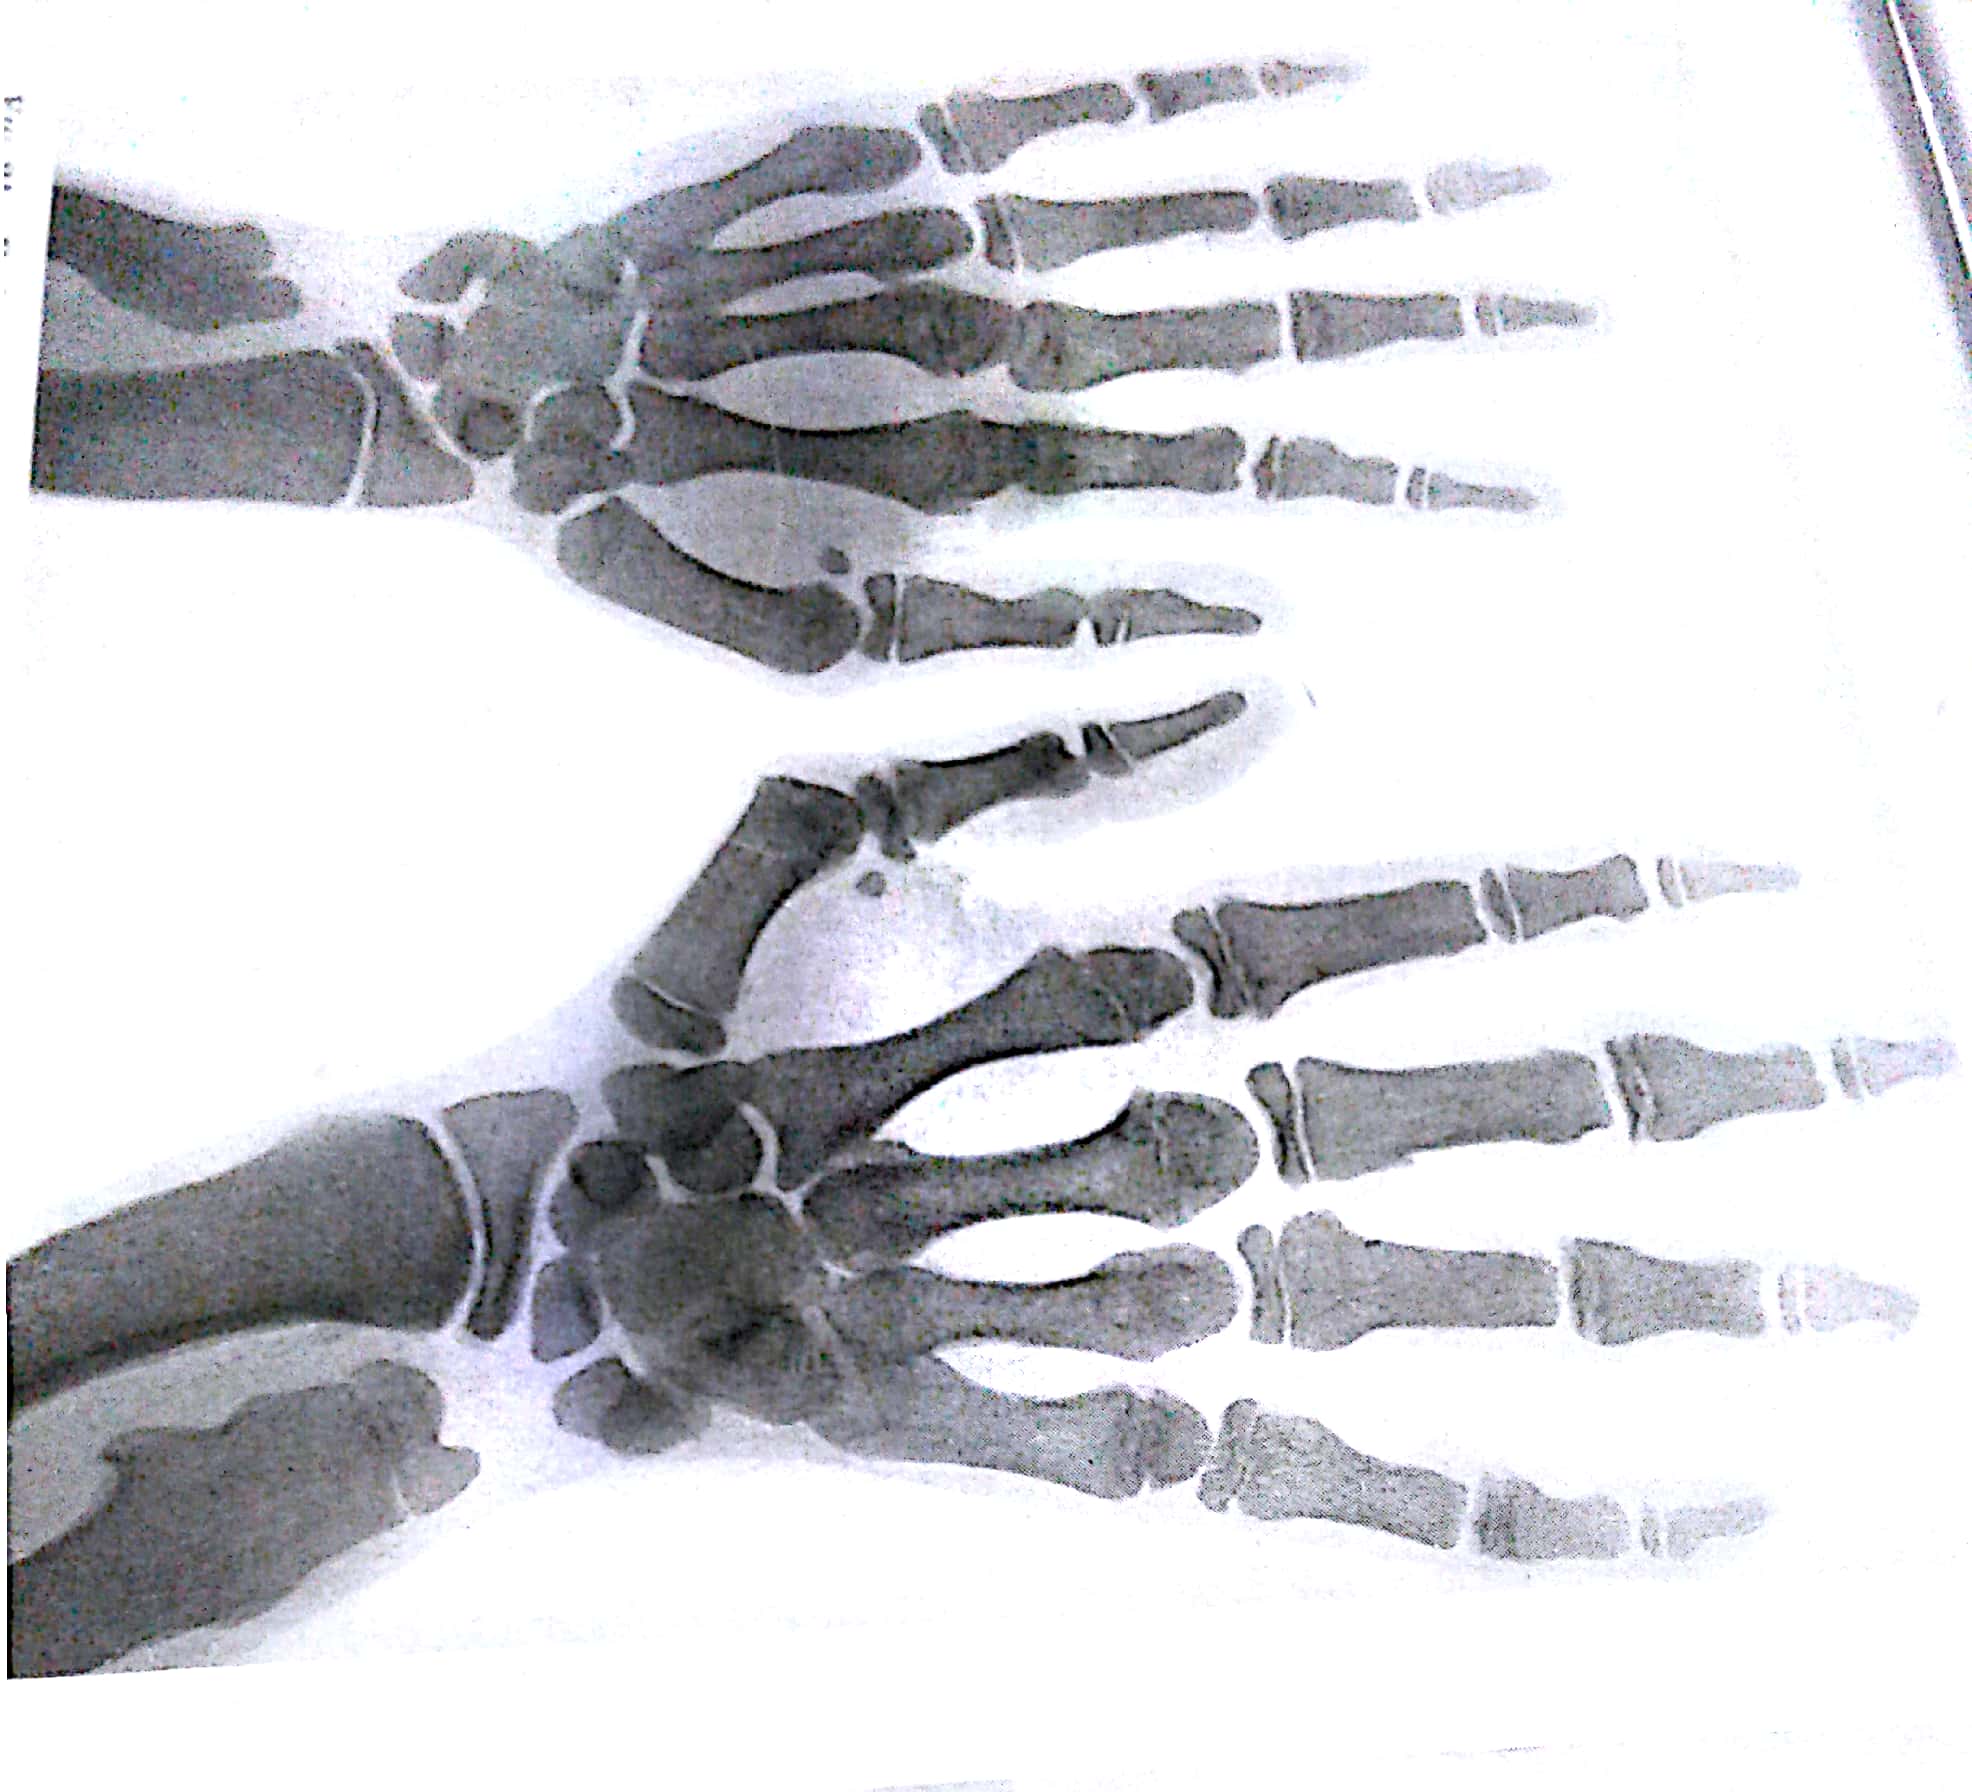

Radiographs of the hand may furnish the observer with much informatrion as to the age of the patient, the presence of familial or congenital deformities, chondro and osseous dystrophies, foreign bodies, localised bone or joint disease or tumour formation, and evidence of specific general skeletal pathology.

Careful attention to the stage of ossification, the regularity of epiphyses, extra epiphyses, the appearances of the compact and cancellous structure and of the growing extremities of the diaphyses will often direct attention to developmental irregularities or pathologiceal changes .

As a genaral ruls it is advisable to expose both hand on the one film,, so that the tow side can be compared.